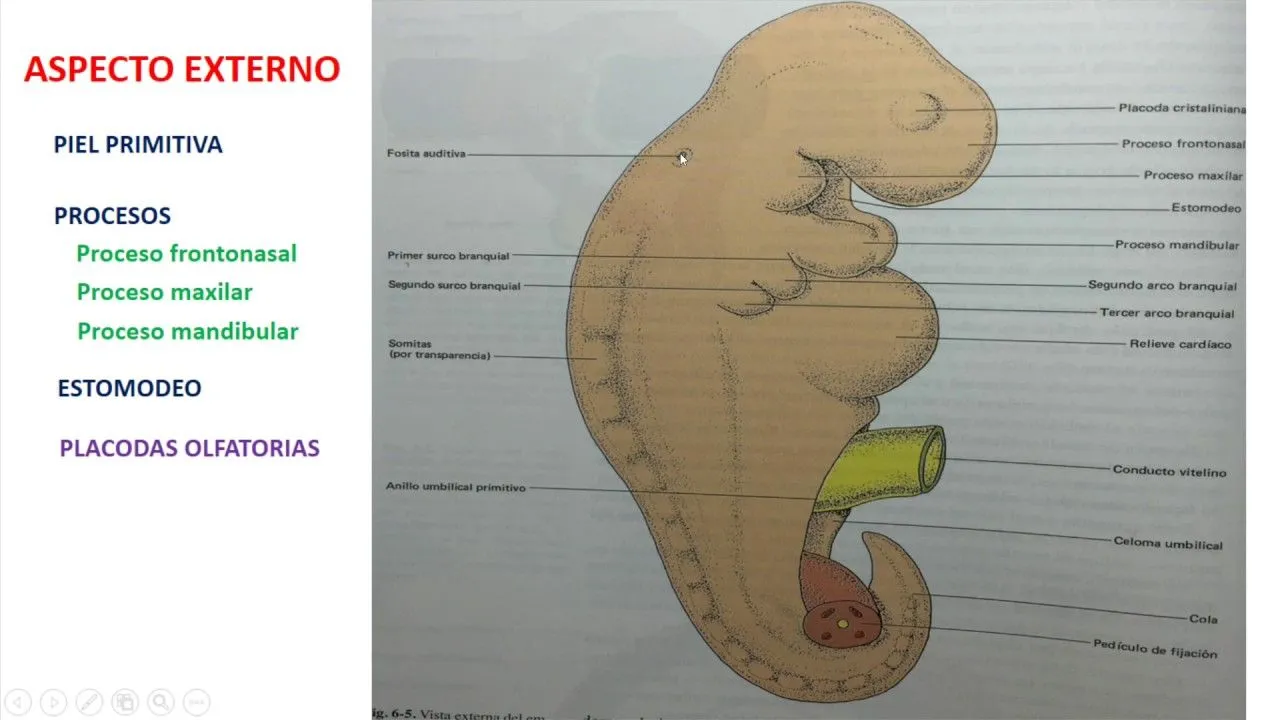

Pin en Imágenes de medicina y anatomía alucinantes